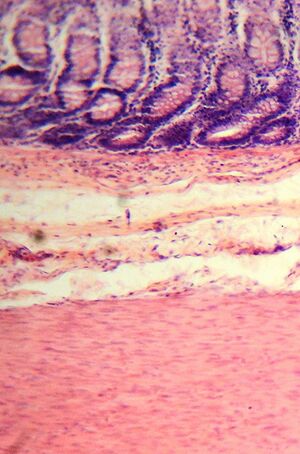

أقبية القولون

جدار الأمعاء الغليظة مبطن بظهارة عمودية بسيطة مع انغماد. تسمى تلك الانغمادات بالغدد المعوية أو خبايا القولون.

صورة مجهرية للخبايا المعوية الكبيرة العادية.

تشريح الخبايا المعوية الكبيرة.

تتشكل خبايا القولون مثل أنابيب اختبار ذات جدران سميكة مجهرية مع وجود ثقب مركزي أسفل طول الأنبوب (خبايا تجويف الأنبوب). يُستعرض هنا أربعة أقسام من الأنسجة، اثنان منها مقطوعان عبر محاور طويلة من الخبايا واثنان مقطوعان بالتوازي مع المحاور الطويلة. في هذه الصور، صبغت الخلايا بواسطة الكيمياء المناعية لإظهار لون بني برتقالي إذا كانت الخلايا تنتج پروتين متقدرة سيتوكروم سي أوكسيديز الوحدة الفرعية I (CCOI). نوى الخلايا (الموجودة على الحواف الخارجية للخلايا المبطنة لجدران الخبايا) مصبوغة باللون الأزرق الرمادي بالهيماتوكسيلين. كما هو موضح في اللوحتين C و D، يبلغ طول الخبايا حوالي 75 إلى 110 خلية.[31] وجد بيكر وزملائه أن متوسط أن متوسط محيط الخبية هو 23 خلية. وبالتالي، من خلال الصور الموضحة هنا، يوجد في المتوسط حوالي 1725 إلى 2530 خلية لكل خبية قولونية. بينما وجد نوتيبوم وزملائه [32] أن قياس عدد الخلايا في عدد صغير من الخبايا سجل نطاقًا يتراوح من 1500 إلى 4900 خلية لكل سرداب القولون. تُنتج الخلايا في قاعدة الخبية وتهاجر لأعلى على طول محور الخبية قبل أن تُلقى في تجويف أنبوب القولون بعد أيام.[31]

كما تم تقديره من الصورة في اللوحة A، يوجد حوالي 100 خبايا القولون لكل مليمتر مربع من ظهارة القولون.[33]

حيث أن متوسط طول القولون البشري 160.5 سم[11] ويبلغ متوسط المحيط الداخلي للقولون 6.2 سم،[33] تبلغ مساحة السطح الداخلي الظهاري للقولون البشري حوالي 995 سم2، الذي يتضمن 9.950.000 (قرابة 10 مليون) خبية.

في أقسام الأنسجة الأربعة الموضحة هنا، تحتوي العديد من الغدد المعوية على خلايا بها طفرة دنا المتقدرة في جين "CCOI" وتظهر في الغالب بيضاء، ولونها الرئيسي هو صباغة النوى باللون الأزرق الرمادي. كما هو موضح في اللوحة B، يبدو أن جزءًا من الخلايا الجذعية لثلاثة خبايا لديه طفرة في "CCOI"، بحيث تشكل 40٪ إلى 50٪ من الخلايا الناشئة عن تلك الخلايا الجذعية قطعة بيضاء في منطقة المقطع العرضي.

بشكل عام ، فإن النسبة المئوية للخبايا التي تعاني من نقص في CCOI أقل من 1٪ قبل عمر 40، لكنها تزداد بعد ذلك خطيًا مع تقدم العمر.[30] تصل خبايا القولون التي تعاني من نقص CCOI لدى النساء، في المتوسط، إلى 18٪ لدى النساء و23٪ لدى الرجال في عمر 80-84 سنة.[30]

يمكن أن تتكاثر خبايا القولون عن طريق الانشطار، كما هو موضح في اللوحة C، حيث تنشطر الخبايا لتشكيل خبيئتين، وفي اللوحة B حيث يبدو أن هناك خبيئة واحد على الأقل تنشطر. توجد معظم الخبايا الناقصة في CCOI في مجموعات من الخبايا (نسخ من الخبايا) مع اثنين أو أكثر من الخبايا التي تعاني من نقص CCOI المجاورة لبعضها البعض (انظر اللوحة D).[30]